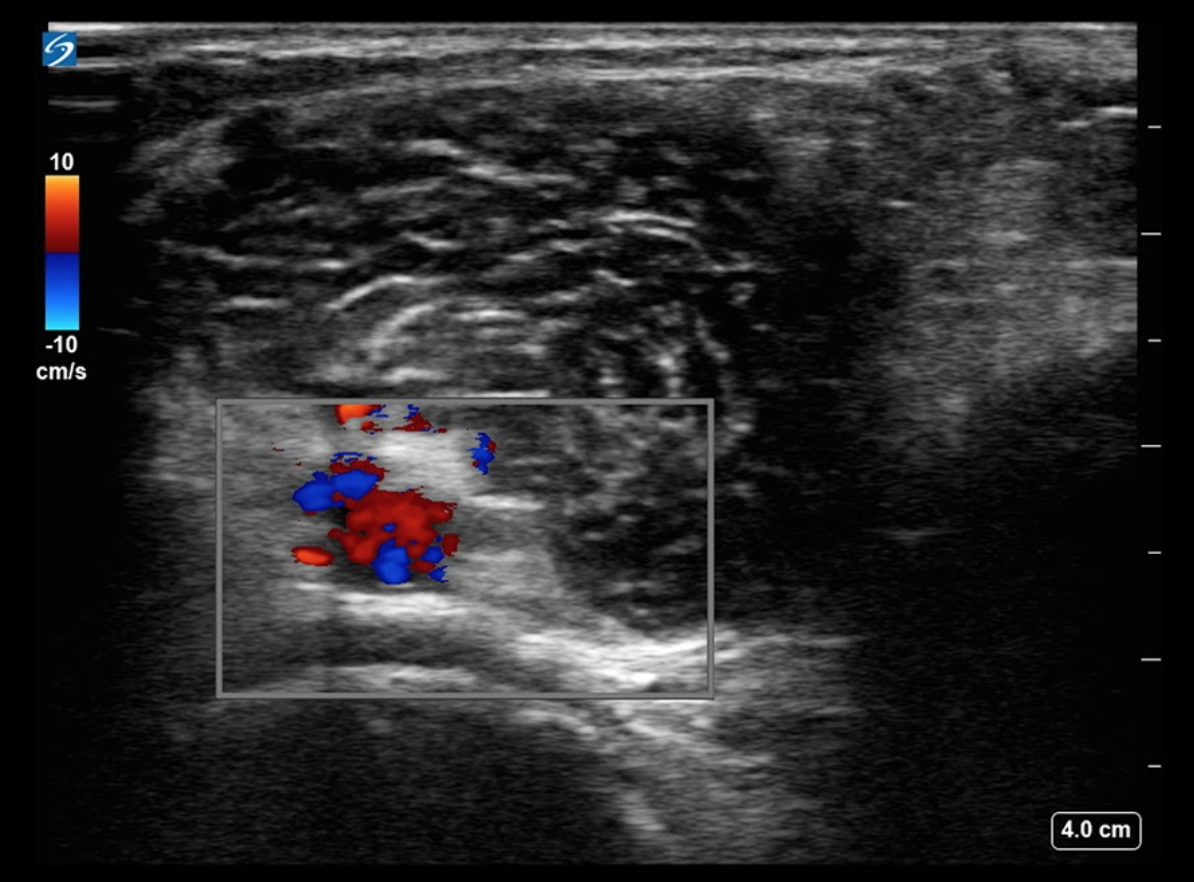

Knee Neurovascular Structures Color Doppler Image